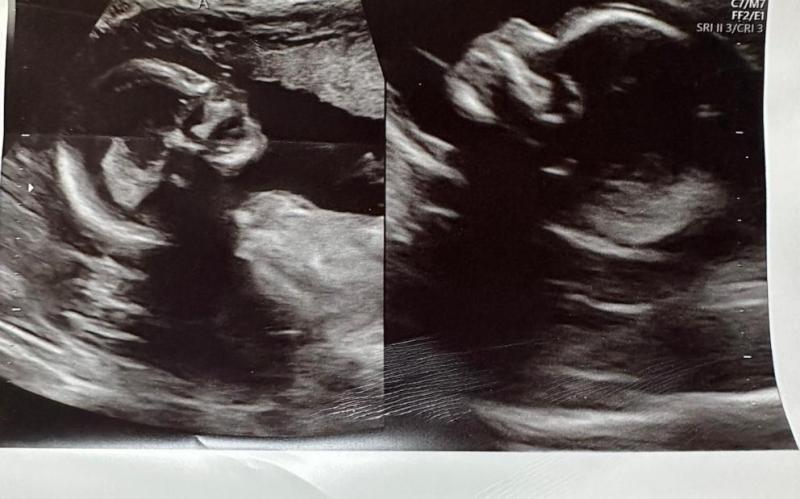

Un extraño caso médico tiene revolucionada a toda la comunidad científica del mundo, puesto que una mujer, que nació con dos úteros, está gestando bebés en ambos órganos.

A pesar que dentro de la condición existe el riesgo de embarazo en ambos vientres, es muy poco probable de que ocurra. Sin embargo, Kelsey se convirtió en el caso 1 en un millón con doble gestación.

La explicación científica de este caso la entregó Shweta Patel, médica obstetra a cargo de la mujer, en Good Morning America, asegurando que los bebés son mellizos no idénticos. "Lo más probable es que cuando esta mujer estaba ovulando, dos óvulos diferentes se posicionaron en cada uno de los úteros, con el esperma viajando hacia cada uno de los vientres, por lo que son dos embarazados diferentes ocurriendo al mismo tiempo".

Foto principal: Kelsey Hatcher para Good Morning America